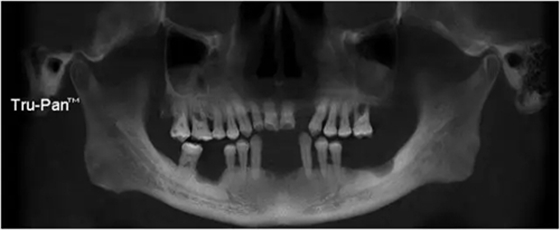

22缺失,21與23之間間隙大于12,切牙齦退縮明顯(圖1)。全景片示 22缺失處齒槽嵴高度和寬度及密度尚可(圖2)。

圖1 術(shù)前口內(nèi)照片

圖2 術(shù)前影像學(xué)檢查